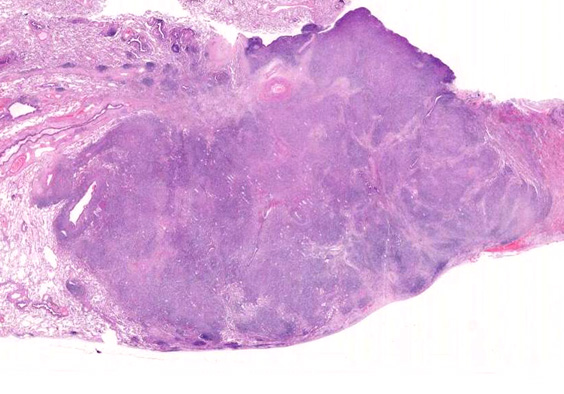

LYGloupe.jpg

VATS採取標本肉眼腫瘤割面像腫瘤組織ルーペ像

病理組織所見